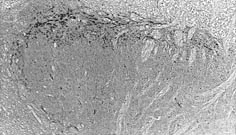

Immunohistochemistry (Formalin/PFA-fixed paraffin-embedded sections) - Anti-Substance P antibody [SP-DE4-21] (AB14184)

AbReview45827****

ab14184 staining Substance P in mouse spinal cord tissue sections by Immunohistochemistry (IHC-P - paraformaldehyde-fixed, paraffin-embedded sections). Tissue was fixed with formaldehyde and blocked with 1% BSA for 10 minutes at 21°C; antigen retrieval was by heat mediation in citric acid. Samples were incubated with primary antibody (1/500 in TBS/BSA/azide) for 2 hours at 21°C. A biotin-conjugated goat anti-mouse IgG polyclonal (1/200) was used as the secondary antibody.

This image is courtesy of an Abreview submitted by Carl Hobbs